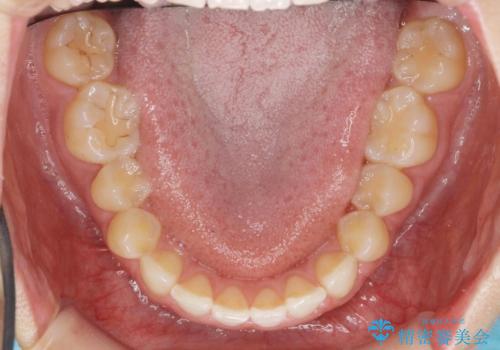

前歯のガタつきをきれいに マウスピース矯正治療

- 「前歯のガタつきをきれいにしたい。」と矯正治療を希望され来院されました。

前歯のガタつきをワイヤー部分矯正、上顎前突の咬合関係を後方移動することで理想的な咬合関係を確立します。

上顎の全体的な後方移動を実現するためにマイクロインプラントを併用したゴムかけを行ったことで理想的な咬合関係を確立することができました。